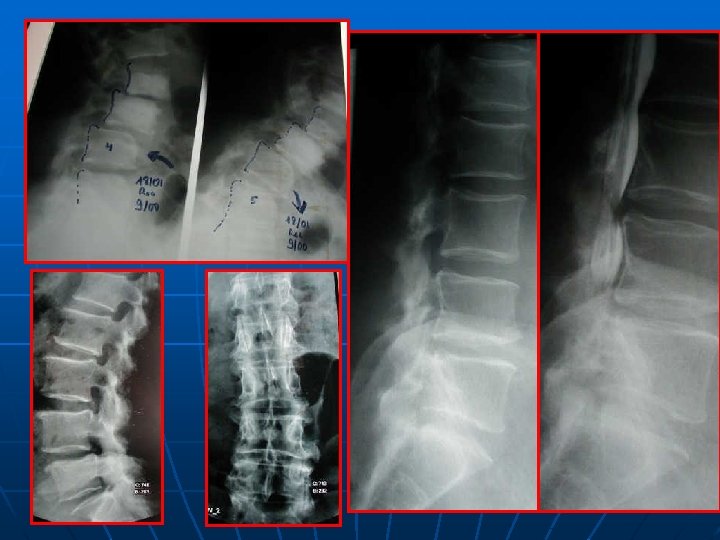

SPONDYLOLESTHESIS ISTHMIQUE Rx standard: face+profil+3/4 D-G Découverte au stade de déplacement n Lombalgies isolées: pas d’autres explorations n Lombosciatiques: Rx dynamiques+ grand format+IRM ( TDM peu d’apport) n

52 ans, spondylo L 5 -S 1 grade I, Beaujon 10